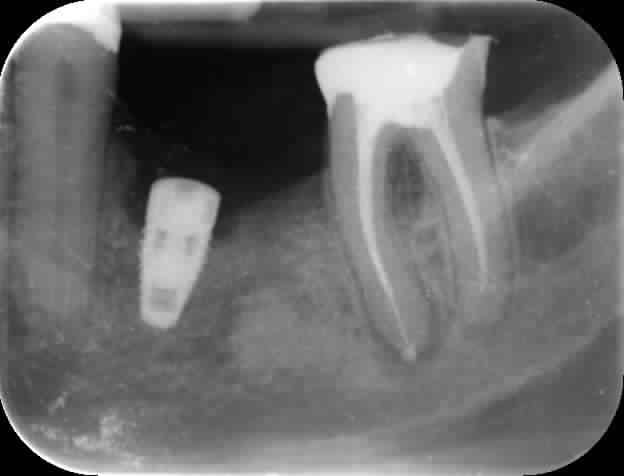

Je pose des implants depuis quelques temps. Pour la première fois, après cicatrisation, j'observe une cratérisation. Tout est asymptômatique mais il est évident qu'il y a un problème.

Bonjour l'ami. Même en restaurant cet impaltn tu auras une large embrasure qui fera garde manger et qui va se charger de detruire le reste sous peu. Vu la longueur d'implant aussi, sans doute une indication plus predictible aurait été un bridge. La prémo semble avoir un énorme compo et la molaire doit etre couronné de tte façon et la crete semble tres mince en plus.

Nobel Replace? (la radio scannée est vraiment mauvaise sur nonol)

Autre question avais tu au moins 1.5 mm de paroi vestibulaire?

Je pense aussi à un problème de largeur de crête osseuse insuffisante.

je pense que tu as eu un problème de souffrance au niveau de la corticale (échauffement, compression...)

J'ai fait faire un cône beam. Je peux essayer de le scanner et de montrer les coupes lundi. Cela dit, la radio que j'ai postée est tellement moche que je ne suis pas sur que vous voyiez grand chose sur ces coupes. Les marges osseuse me semblaient bonnes en vestibulaire notamment. Peut être ai je trop forcé lors du vissage? J'avoue ne pas avoir encore beaucoup d'expérience et donc de sensation lors de la mise en place.

donc j'ai vu juste avec le Nobel replace...

observe bien la forme de cet implant, regarde ces spires, l’absence de "lames de coupes" à l'apex et tu en déduiras toi même son comportement dans l'os...

c'est un implant compressif, non autotaraudant, voilà pourquoi je t'ai demandé si tu avais taraudé

dans du D4 il n'y aurait pas eu de problème mais là, tu as écrasé ton os cortical au point d'engendrer une lyse et donc une cratérisation...

bilan, la prochaine fois que tu l'utiliseras (et ce surtout à la mandibule...) dès que tu auras un os dense => taraud et autre règle, pas plus de 45/50 Ncm de couple de serrage...;-)

Un implant de 8,6 mm ( les tapered 8 de Nobel font 8,6) c'est assez long à la mandibule

Le seul truc moche c'est la position et l'axe: erreur de débutant : on a tendance au début a "piocher" les implants ..... Remède : East Guide de Clio (Dr Cazalbou faire une recherche google) et prolongateur de foret pour rester dans les bons axes